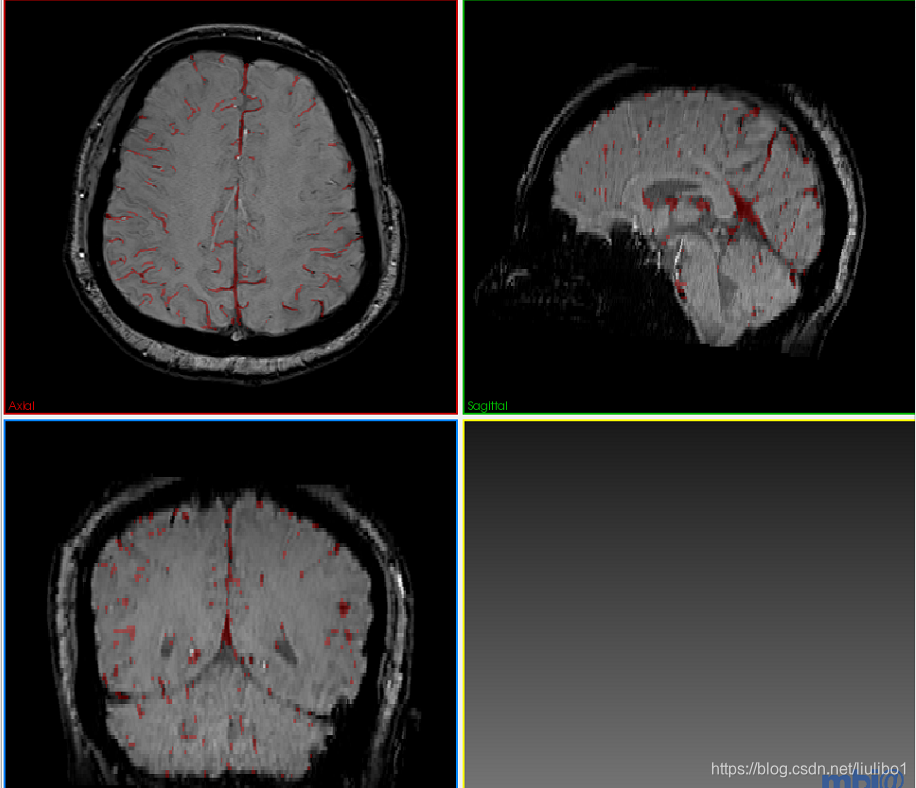

我这里写了3D元素的代码,有兴趣的同志可以改成2D的。(这里使用的是脑部MRI的数据,我们想做的是将脑组织提取出来,即将MRI影像中的颅骨等非脑部组织去掉,以便我们分割静脉)